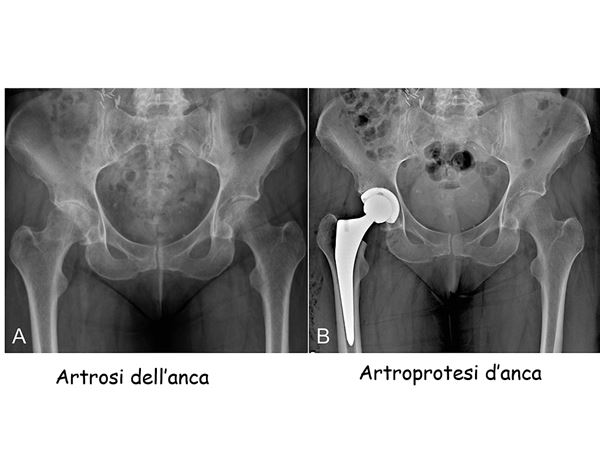

artrosi anca